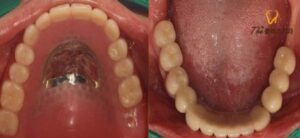

먼저 구강에 맞는 틀을

인상 채득한 후 제작하게 되는데

이때 틀은 조금 더 정확한 구강 상태를

채득하기 위한 과정으로,

만들어진 틀에 정밀한 인상 채득 재료를 사용하여

틀니를 위한 최종 인상을 하게 됩니다.

이때 틀니의 내면이

적합하게 만들어지기 위해서는

정밀한 인상 채득을 하는 것이 무엇보다 중요합니다.